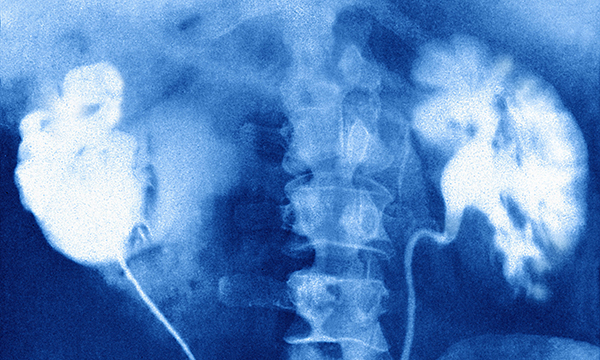

Nurses should help educate older people and carers about risks associated with acute kidney injury for which follow-up and continued monitoring are crucial